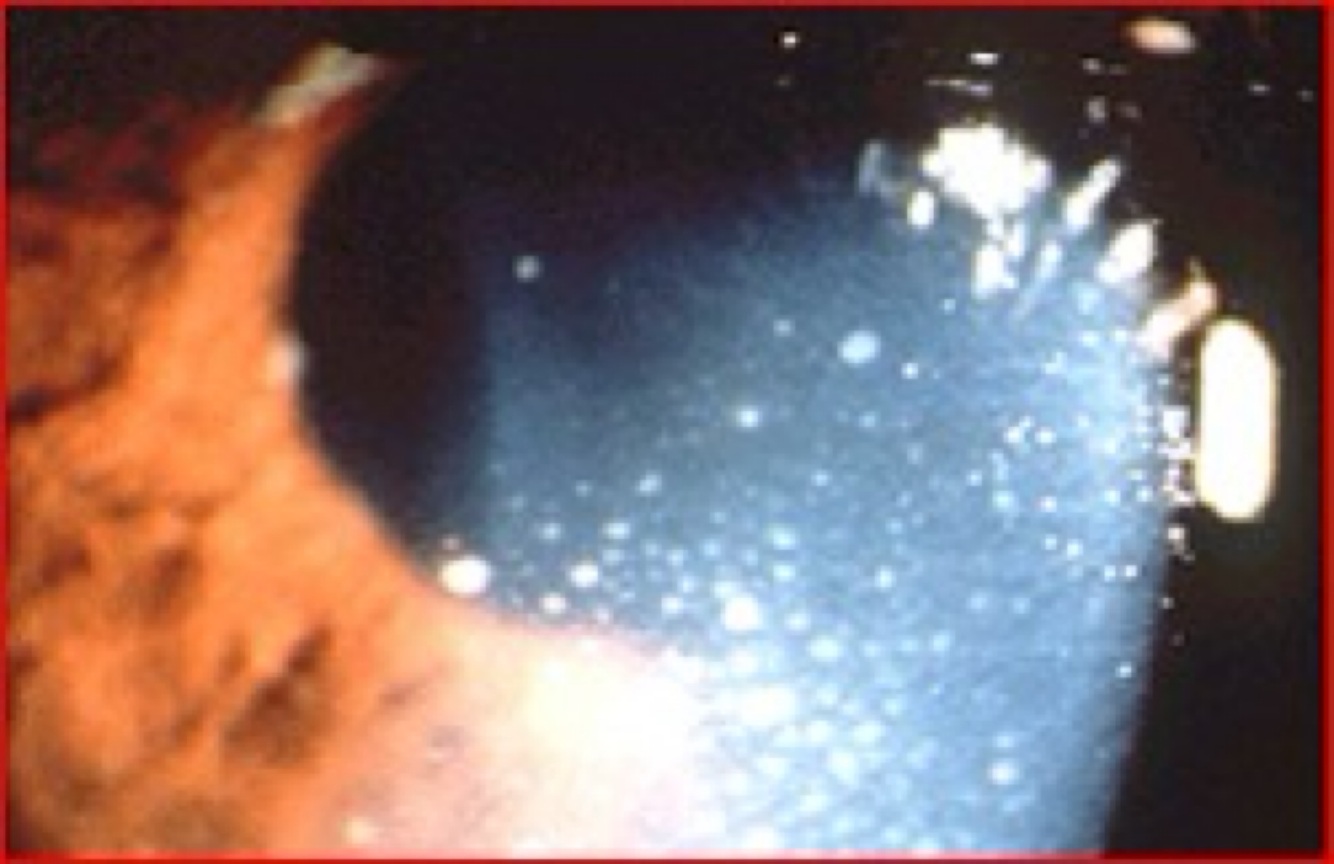

¿Qué observas en la siguiente imagen?

Reacción ciliar

Celularidad